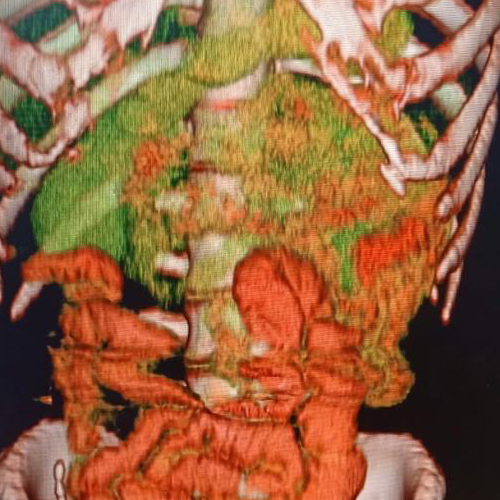

Best Scanning Center In Nakodar